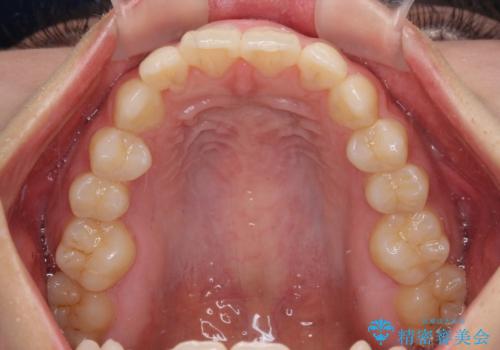

- 下顎前歯に乳歯が残っており、欠損もしていることを気にして来院された患者様です。

舌の突出癖が顕著にあり、上下前歯が非接触となっており、上顎前歯が前方に突出している状態でした。

ワイヤー装置により矯正治療を行うとともに舌突出癖改善のためのトレーニングをしっかりと行っていただき、咬み合わせが安定した位置となったタイミングで下顎前歯にブリッジの仮歯を装着していく計画としました。

矯正治療終了後に速やかにオールセラミックブリッジを装着していくこととしました。